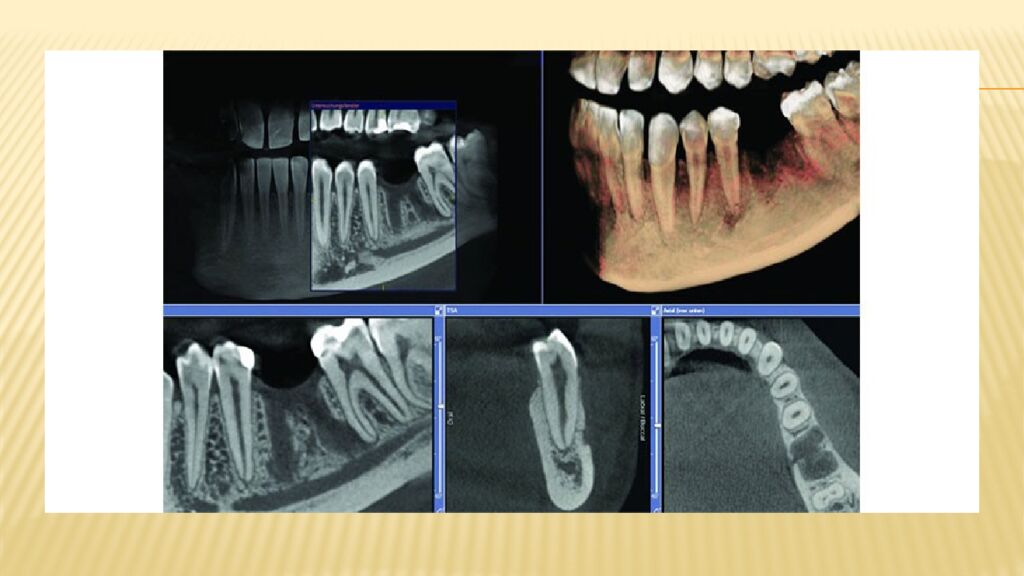

• КЛКТ кезінде алынатын суреттер

Конусты-сәулелі компьютерлік томография (КЛКТ) Бұл зерттеу алынатын сәулеленудің ең төменгі дозасымен сипатталады, әрі түсірілім дәстүрлі рентгендік аппаратпен жүргізілетін тексеріспен салыстырғанда анағұрлым ақпаратты болып шығады. Жақ сүйектерінің КЛКТ- сы (конус- сәулелі компьютерлік томография) жақ -бет аймағын зерттеуге қолданылатын көлемді сандық зерттеулер қатарына жатады. Үшөлшемді бейнелер арнайы бағдарламалық қосымшалардың көмегімен алынады. Бейнелердің сапасы жоғары болуы үшін пациент процедура бойы толық қимылсыз қалуы тиіс. Басты иммобилизациялау құралдары арқылы белгілі бір қалыпта бекіткеннен кейін, конус- сәулелі компьютерлік томограф оның айналасында айналмалы қозғалыс жасайды. Аппараттың бір жағында рентген сәулесінің көзі, екінші жағында – қабылдағыш орналасады. Томограф компьютерге қосылады және барлық алынған ақпарат сол жерде өңделеді.

Тексеру барысында аппарат зерттелетін аймақтың жалпы жағдайын көрсететін көптеген түсірілім жасайды. Бұл суреттердің диагностикалық құндылығы болуы үшін маман оларды арнайы бағдарламалар арқылы өңдейді. Бұл қажетті аймақты әртүрлі проекцияларда қарауға, тіндердің құрылымдарын өлшеуге, сондай-ақ диагноз қоюмен айналысатын бейінді маманға арналған үшөлшемді модель құруға мүмкіндік береді. Мысал ретінде суретте көруге болатындар тізімі : Тісті қоршаған жұмсақ тіндердің жағдайы. Сүйек тіндерінің құрылымдық патологиялары : атрофия, остеопороз, остеонекроз және т.б. Сүйек құрылымдарының патологиялық өзгерістері. Түсірілімдерде үзіктер, талшықтану және басқа да жағымсыз процестер анық көрінеді. Тіс түбірі өзектерінің жағдайын талдау. Тіс қаптамаларының ( коронкалардың ) ақаулары және тағы басқалар.